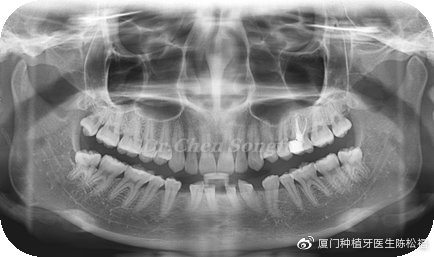

患者情况:E女士,24岁,下前牙先天缺失,存在散在间隙,覆合过深。

检查结果:下前牙从小存在间隙,影响美观。全口牙周情况良好,口腔卫生尚可。32,42缺失,41,31,43,33移位存多处散在间隙。咬合关系基本正常,前牙区深覆合

方案设计:行全口正畸治疗,31,41,33,43前移关闭前牙正中区间隙,预留33,43位置,改善前牙深覆合,33,43各种植一颗植体,完成最终修复。